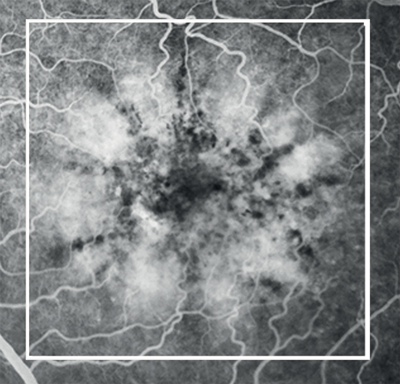

Figures 1-4: Swept-source OCT (DRI OCT-1 Triton, Topcon) images of healthy eyes that clearly delineate features in the vitreous, including area of Martegiani, bursa premacularis and posterior hyaloid, right through to the sclera, in the same single scan.

Figures 8 and 9: Case examples from clinical sites: choroidal neovascularisation associated with AMD visualised using fluorescein angiography and optical coherence tomography angiography (images courtesy of Optovue, Inc, CA, USA).